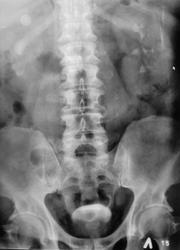

Пациент с диагнозом "МКБ" направлен на обзорную рентгенографию почек и мочевыводящих путей.

Пациент с диагнозом "МКБ" направлен на обзорную рентгенографию

Внутривенная урография.

На мой взгляд дополнительная интенсивная тень лежит за контуром почки. В проекции Желчного пузыря. Так что желчекаменная болезнь? Рекомендованно УЗИ печени и желчного пузыря.

Да с камнем желчного то все понятно...но вот тень в проекции н\трети правого мочеточника ....весьма необычна...вопрос - куда ее "пристроить"?))))

Да, камешек для желчного типичный.

А тень в дистальной трети мочеточника действительно "фердиперсовая"...